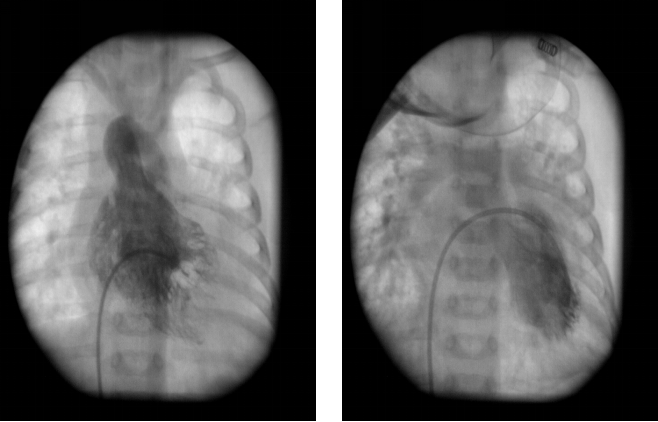

完全性大动脉换位:心血管造影表现

◇ 右室压力与主动脉相等,肺动脉血氧饱和度高于主动脉

◇ 主动脉发自右室,肺动脉发自左室,主动脉空间位置异常并可显示是否合并冠状动脉畸形